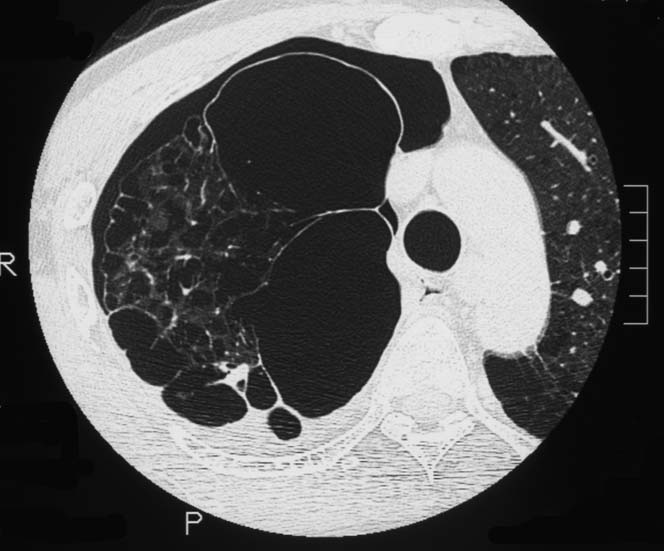

5ヵ月後右主気管支を圧迫しほとんど閉塞する巨大な腫瘍を認めた. 他院で緊急放射線療法および化学療法を行うが効果なし. 腫瘍切除+右肺上葉切除をおこない肉眼的には腫瘍は完全切除できた. 病理診断は非典型的であるが malignant SFT. 当院に再入院, radiation therapyをおこなう. 効果乏しく, 腫瘍は進行し呼吸不全で永眠される.

胸腔鏡下ブラ切除術5ヵ月後, 縦隔腫瘤で再発. 他院で腫瘍切除+右肺上葉切除を施行. 肉眼的には腫瘍は完全に切除できた.

初診から11ヵ月, 胸部つかえ感出現. CTで気管分岐部から横隔膜食道裂孔を通り, 腹腔内へ進展, 食道および大動脈を囲繞する巨大な腫瘍が再発した. 他院での抗がん剤感受性テストの結果より, CDDP+5FUによる化学療法がおこなわれたが効果乏しく全身状態悪化. 呼吸不全が進行し初診より約1年の経過で永眠された.